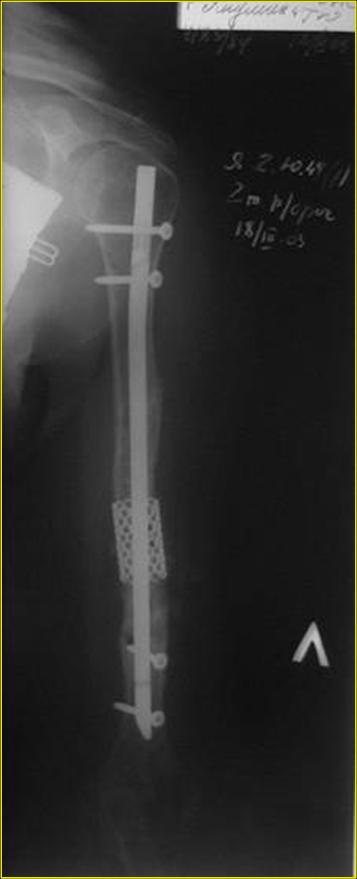

Типичная положительная ситуация для интрамедуллярного остеосинтеза с

использованием опорного металлокаркаса для компенсации дефекта.

Послеоперационное ведение активное или агрессивно-активное. Каркасы

можно заказать в МАТИ.

Рентгеновская версия реконструкции. хронология:

после операции, 2 мес. после операции, через 1 год

Движения в полном объеме восстановлены к 2 мес. после операции. Если надо могу показать мультик. Сейчас уже прошло более 3 лет, больная не

показывается. Успехов ЛАФ.